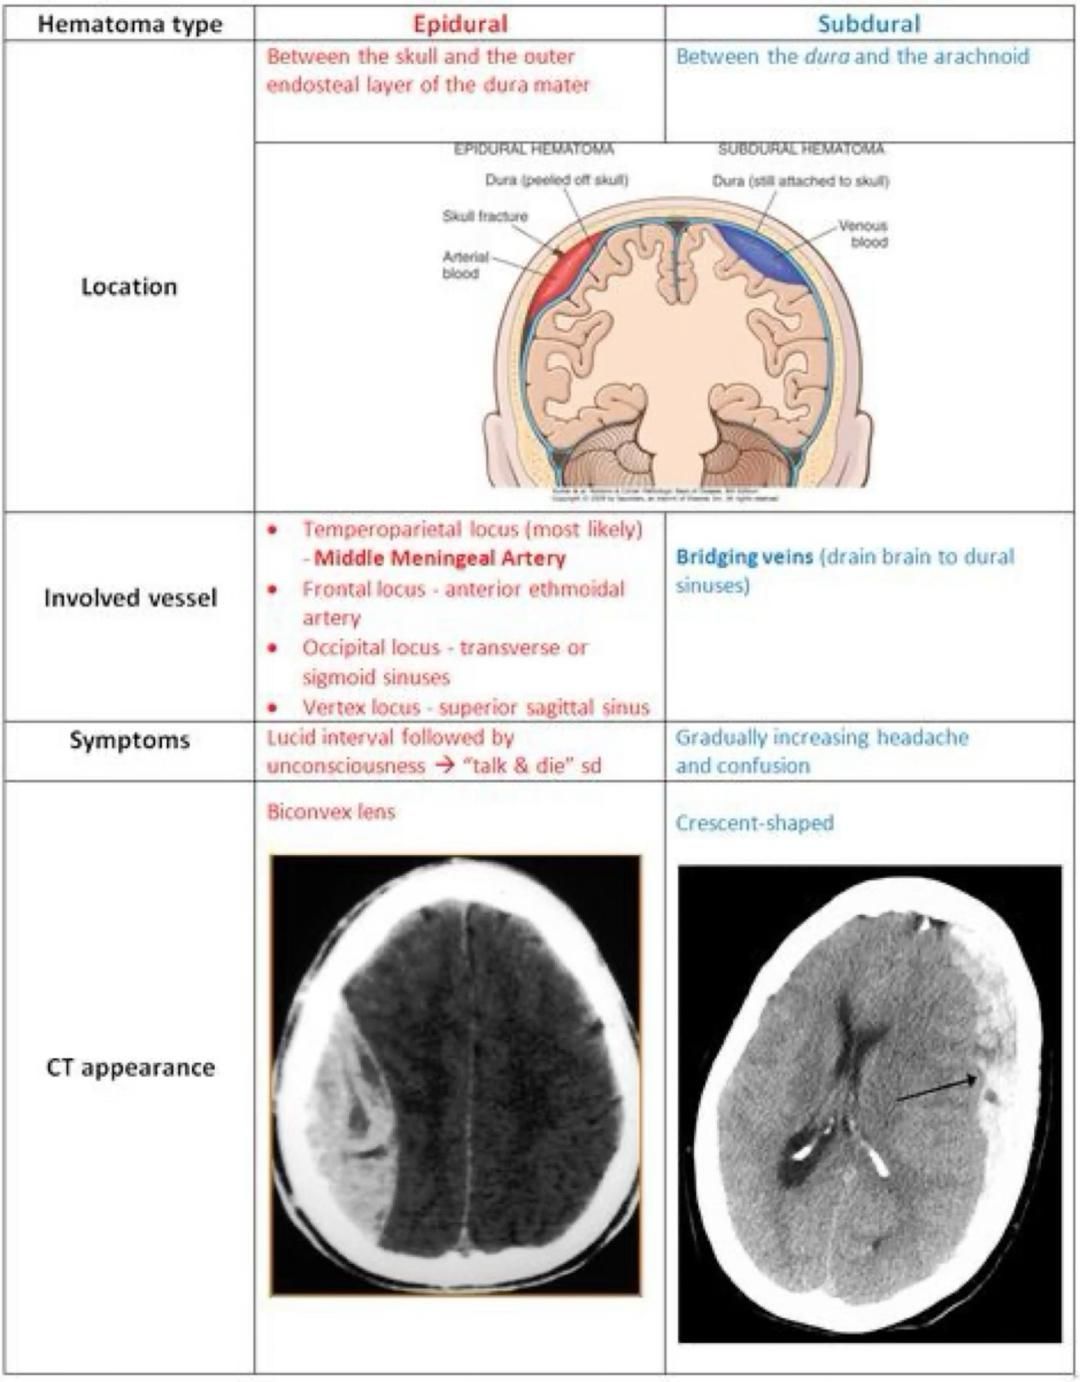

Understand the key differences between a subdural vs epidural hematoma. This guide compares the causes, symptoms, and critical diagnostic features of these intracranial hemorrhages. Learn how brain anatomy, traumatic brain injury mechanisms, and clinical urgency distinguish these life-threatening conditions to help you recognize when immediate neurosurgical intervention is required for improved patient outcomes.